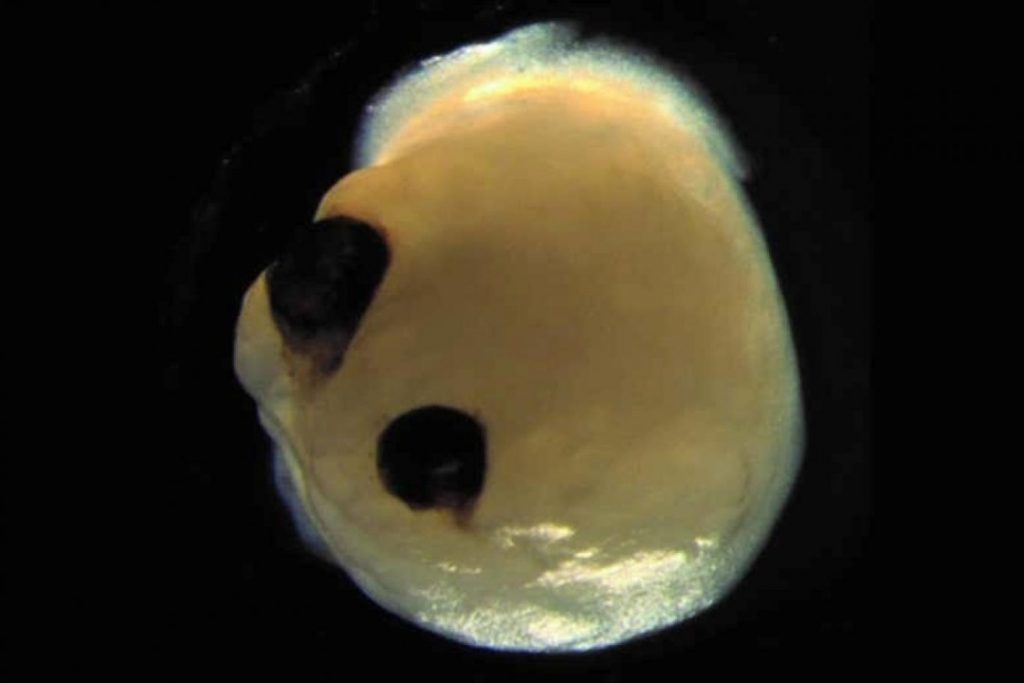

به گزارش خط بازار، دانشمندان بر مبنای یک پژوهش، «مغزهای آزمایشگاهی» کوچکی را کشت دادهاند که «چشمهای» حساس به نور ایجاد کرده است. تیمی از محققان برای ایجاد ارگانوییدها (اندامواره) از سلولهای بنیادی «همهتوان» القا شده انسانی استفاده کردند. انداموارهها ساختارهای بافت چندسلولی سه بعدیاند که [خصوصیات] اندام مربوطه را تقلید میکنند و [از این رو] در آزمایشگاهها از آنها برای اهداف تحقیقاتی استفاده میشود.

در سیامین روز تحقیق دانشمندان، انداموارههای مغز تلاش کردند که حبابهای بینایی (vesicle optic) را گرد هم بیاورند. حبابهای بینایی، بیرونزدگیهای رشد یافته مغزند که چشمها از آنها شروع به رشد میکنند.

به گفته محققان، این حبابهای بینایی در مدت ۶۰ روز تا تبدیل شدن به ساختارهای قابل رویت رشد میکنند. دانشمندان میگویند که یافتههای آنها به دانش موجود در زمینه ترکیببندی مغز-چشم در مدت رشد جنین رویان خواهد افزود و به درک بهتر اختلالات شبکیه کمک خواهد کرد.